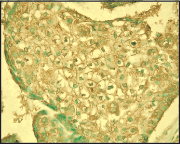

Detection of human EpCAM by staining paraffin sections. Sample: Human breast carcinoma. Primary antibody: Anti-EpCAM (Ab-1) Mouse mAb (1Dg.F3) (Cat. No. CP63) (2.5 μg/ml). Detection: DAB